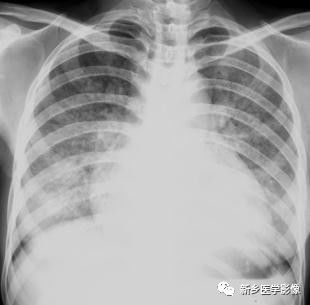

肺水肿X线图像:正位片示双肺呈大片阴影,右侧较明显,心影亦见增大